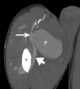

Traumatic arteriovenous fistula